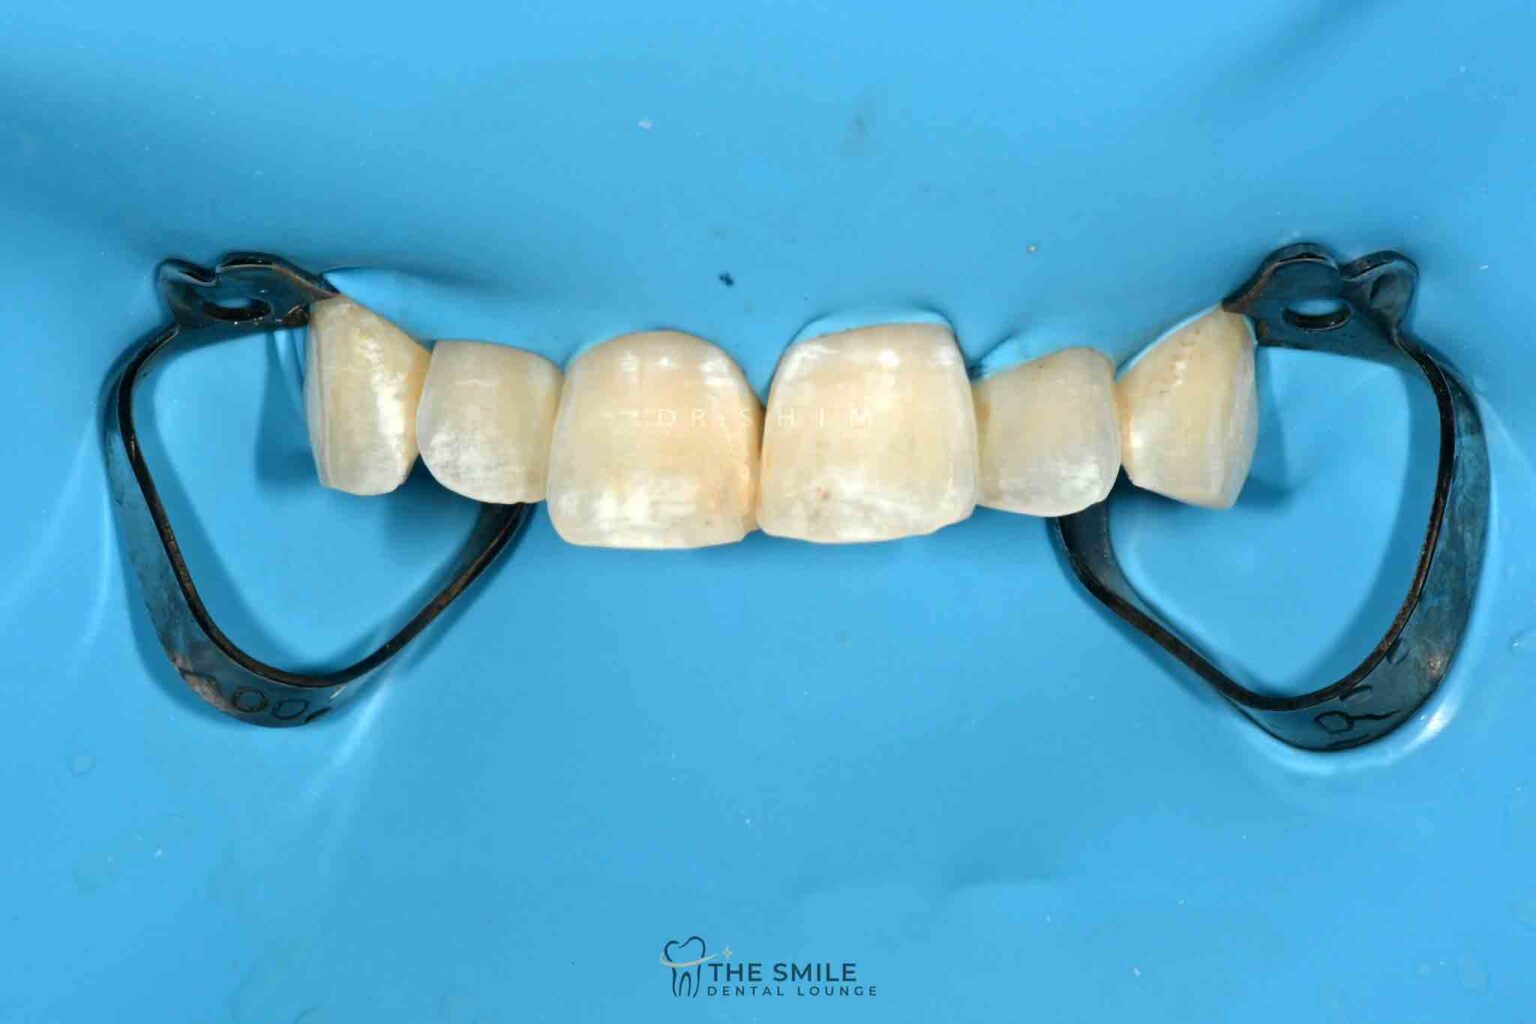

Resin infiltration procedure in tooth 11 (a) Rubber dam isolation of Where Is Resin Infiltration Most Successfully Used resin infiltration seems to be a clinically effective method in arresting. the icon (infiltration concept) was designed as a minimally invasive resin infiltration system for treating incipient caries in patients of all. They were informed that the process may need to be repeated several times in order to treat deeper lesions. the principle of resin infiltration is. Where Is Resin Infiltration Most Successfully Used.

From www.researchgate.net

Resin infiltration procedure in tooth 11 (a) Rubber dam isolation of Where Is Resin Infiltration Most Successfully Used the principle of resin infiltration is to perfuse the porous enamel with resin by capillary action, thereby arresting lesion. It seals the porosity of the. They were informed that the process may need to be repeated several times in order to treat deeper lesions. the icon (infiltration concept) was designed as a minimally invasive resin infiltration system for. Where Is Resin Infiltration Most Successfully Used.